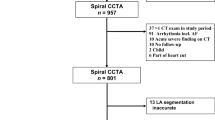

An IRB-approved, retrospective review from January 2012 through May 2014 was performed at a single US academic medical center. The review identified all adult advanced heart failure patients treated with an ICD who were being evaluated for either LVAD placement or heart transplantation. All patients were included who underwent left and right ventricular function evaluation with both cardiac MRI and radionuclide angiography within 120 days. A comparison of the calculated left and right ventricular ejection functions was performed comparing cardiac MRI with radionuclide angiography. The electronic medical record for each patient who met inclusion criteria was reviewed for the clinical course, specifically whether the patient went on to receive a LVAD. Medical record review also included performance of any echocardiogram or right heart catheterization performed during the evaluation period. While these exams do not provide a calculated ejection fraction, that right ventricular functional parameters from these exams have been shown to be predictive of post-operative right ventricular failure after LVAD placement [41].

Nine patients including 8 (89%) men and 1 (11%) woman with a mean age of the patients was 57.0 years (median: 60.0, range: 28 - 66) underwent ventricular ejection fraction evaluation with both cardiac MRI and radionuclide angiography for pre-operative heart failure evaluation for planning of LVAD placement or heart transplantation. Four patients were diagnosed with ischemic cardiomyopathy, and 5 patients were diagnosed with nonischemic cardiomyopathy. The average time interval between the cardiac MRI and radionuclide angiography (MUGA and FPRNA) was 38.9 days (range: 1 - 119 days). The average dose of intravenously administered technetium-99 m labeled RBCs for radionuclide angiography was 23.0 mCi (range 20.1 – 25.0 mCi).